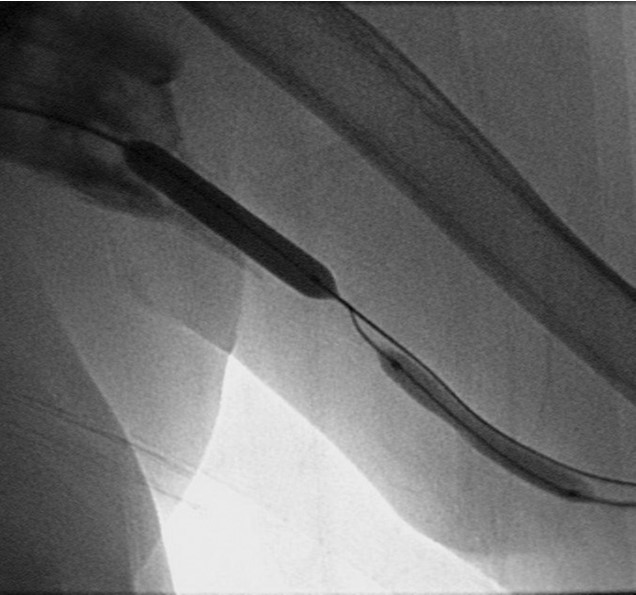

환자의 AV fistula는 초음파상 total thrombotic occlusion 된 상태였으며 시술 전 urokinase 100000 unit를 사용하여 thrombolysis and aspirated thrombectomy를 시행하였다. 그 후 시행한 shuntogram(Fig. 1) 상 left basilic vein 의 total ocdusion을 보이며 초음파상 remant vein의 크기는 1mm 이하로 확인되었다. 투시하에서 확인되는 outflow vein은 없었기에 초음파 유도하에 5 Fr Kumpe catheter(Soft-Vu, AngioDynamics, USA, NY) 에 0.035’ straight-tip guide wire(Terumo, Tokyo, Japan)를 사용하여 막힌 left basilic vein으로 15cm 이상 진행하였으며(Fig. 3), 4mm balloon (synergy, Boston, Ireland)를 사용하여 blind angioplasty를 하며 true lumen으로의 진행을 시도하였으나 실패하였다(Fig. 4). 더 이상의 antegrade로의 접근은 어려울 것으로 판단하여 regrograde approach를 위하여 left internal jugular vein 을 초음파 유도하에 9Fr sheath( Accu-Sheath, Sungwonmedical, Korea, Cheongju)을 사용하여 access 하였다. (Fig. 5A) 그리고 5Fr Cobra & sherpherd hook catheter (A&A M.D., Korea, Sungnam) 를 이용하여 left axillary vein으로의 접근을 시도하였다(Fig. 5B).

Fig. 4.

A-B. Failure of guide wire negotiation. Balloon tip was located in subcutaneous tissue.